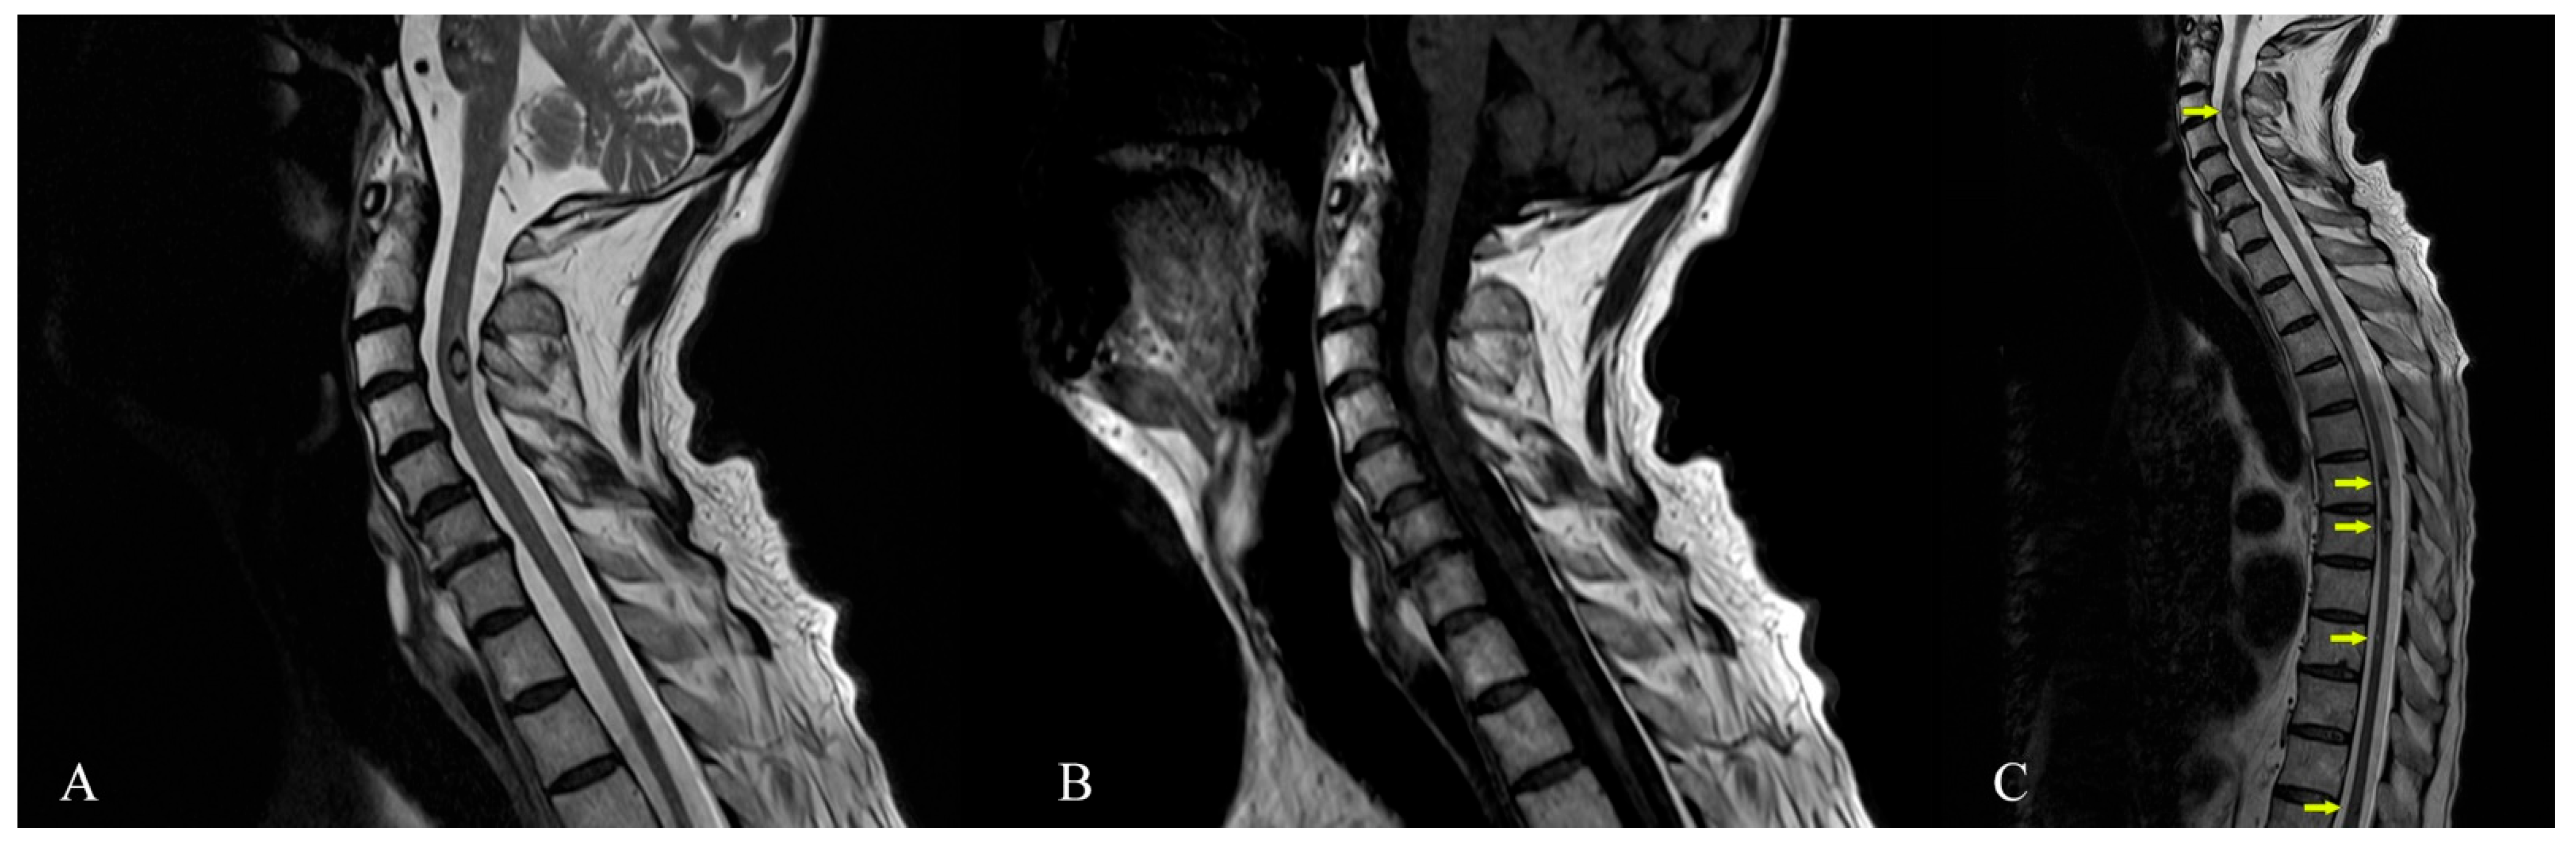

Magnetic Resonance Imaging of Multiple Cerebral and Spinal Cavernous Malformations of a Patient with Dementia and Tetraparesis

Antonescu, F.; Butnariu, I.; Cojocaru, F.M.; Anghel, D.N.; Antonescu-Ghelmez, D.; Tuță, S. Magnetic Resonance Imaging of Multiple Cerebral and Spinal Cavernous Malformations of a Patient with Dementia and Tetraparesis. Diagnostics 2022, 12, 677. https://doi.org/10.3390/diagnostics12030677